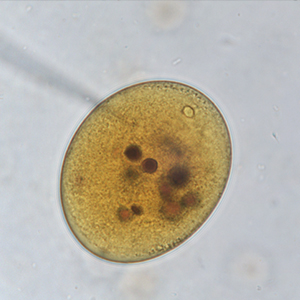

Le kyste est sphérique à ovoïde, à paroi épaisse, mesurant 50 à 100 μm de diamètre. Il présente un contenu granuleux, un macronucléus et micronucléus difficilement visibles (Strait et al., 2012). La coloration au Lugol permet de mettre en évidence certains organites qui apparaissent en brun sombre, de colorer la paroi en brun et l’intérieur du kyste en jaune.